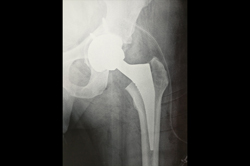

Total Hip Replacement - THR